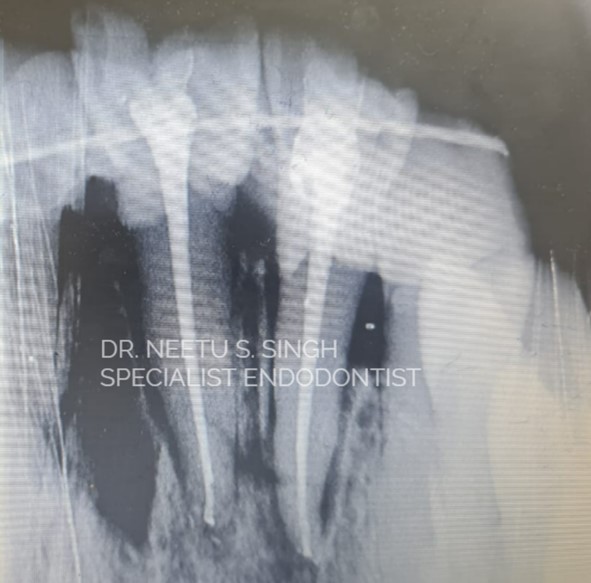

Teeth were properly cleaned and Root canal Treatment was done while holding the tooth in the hands. This entire procedure was done by Dr. Neetu S. Singh Specialist Endodontist. She took a pre–op x-ray to assess the socket.

Immediately after placement into the socket and splinting.

Follow up of the after six months patient. The Tooth is firmly back in its socket.